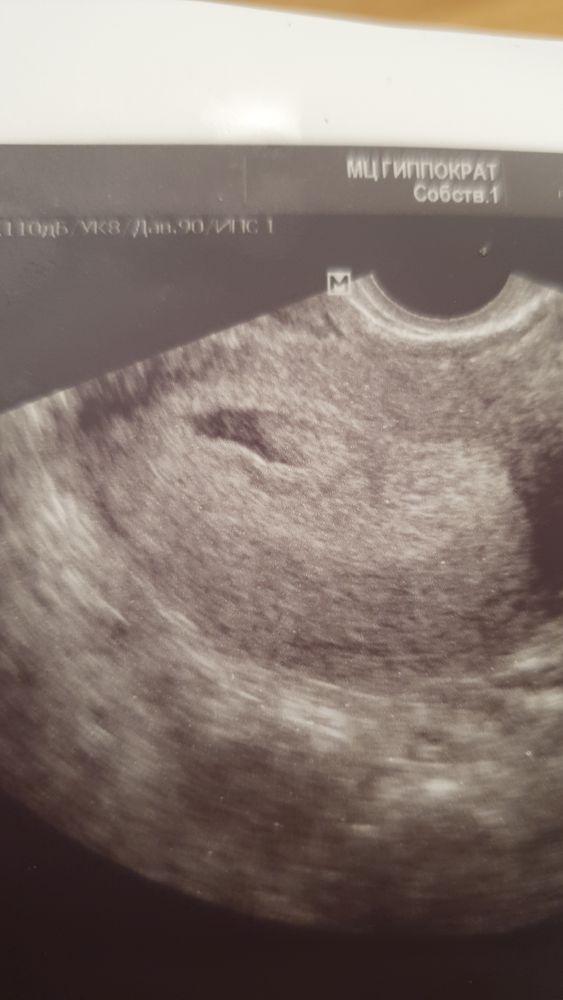

Марина, Надеюсь, первые. Фото с УЗИ есть, крошку-эмбриона видно 😍

Марина, Помогите разобраться тогда) Плодное яйцо 15 мм, КТР 4,8мм

aleksa-doctor, вообще ваше УЗИ на срок 6+1 примерно акушерских,у меня в 6+2 пя было 19 мм,ктр 5,4 мм и сб 146 уд/мин,но хгч за 4 дня до УЗИ 38499 был уже, странно за 5 дней у вас не мог же хгч вырасти в несколько тысяч,а тест яркий хоть?

aleksa-doctor, непонимаю как такое возможно,и сердцебиение было? Единственное что в голову приходит, аппарат заглючил и картинка осталась от предыдущего пациента

Марина, нет, СБ не было

aleksa-doctor, а при таком ктр должно быть,может все таки картинка с УЗИ не ваша была,не сходится хгч,тесты и узи совершенно и по сроку у вас рано

aleksa-doctor, ну при таком ктр уже должно быть сердцебиение, чья-то ошибка🤷‍♀️

aleksa-doctor, вы канечно извините но тут еле видно плодное,у меня при плодном яйце 17.5 только ЖМ было и то ставили ровно 5 недель.Через 10 дней,а это уже 3 недели задержки увидели И эмбриона и все,и мы как раз выросли хорошо поставили по сроку месячных.